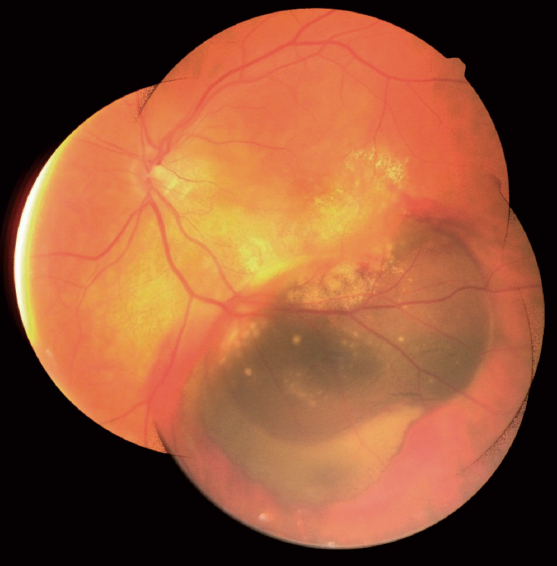

Indirect ophthalmoscopy along the course of the inferior vascular arcade visualized a mass oval-shaped lesion, dark, protruding into the vitreous, and 5 × 6 optic nerve head diameters in size. Accumulation of the subretinal material (organized blood) and blood was determined along the lower peripheral edge of the neoplasm, and hard exudates were noted along the central edge with the involvement of the macular center (Fig. 1).

Fig. 1. Color fundus photography with oval mass / Рис. 1. Фотография глазного дна с объёмным образованием овальной формы